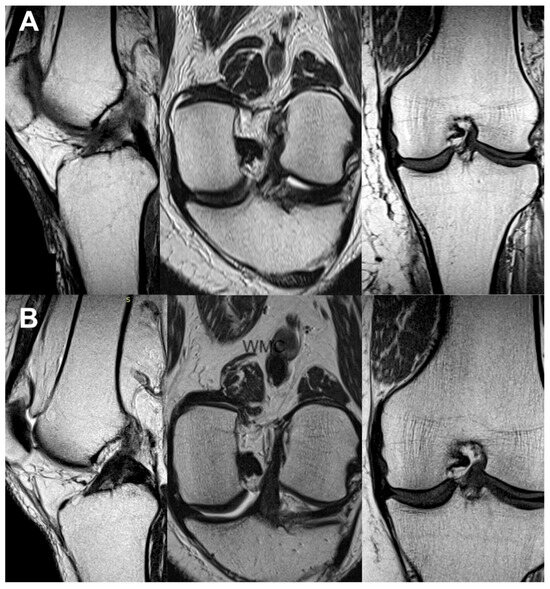

3.3. Imaging Analysis